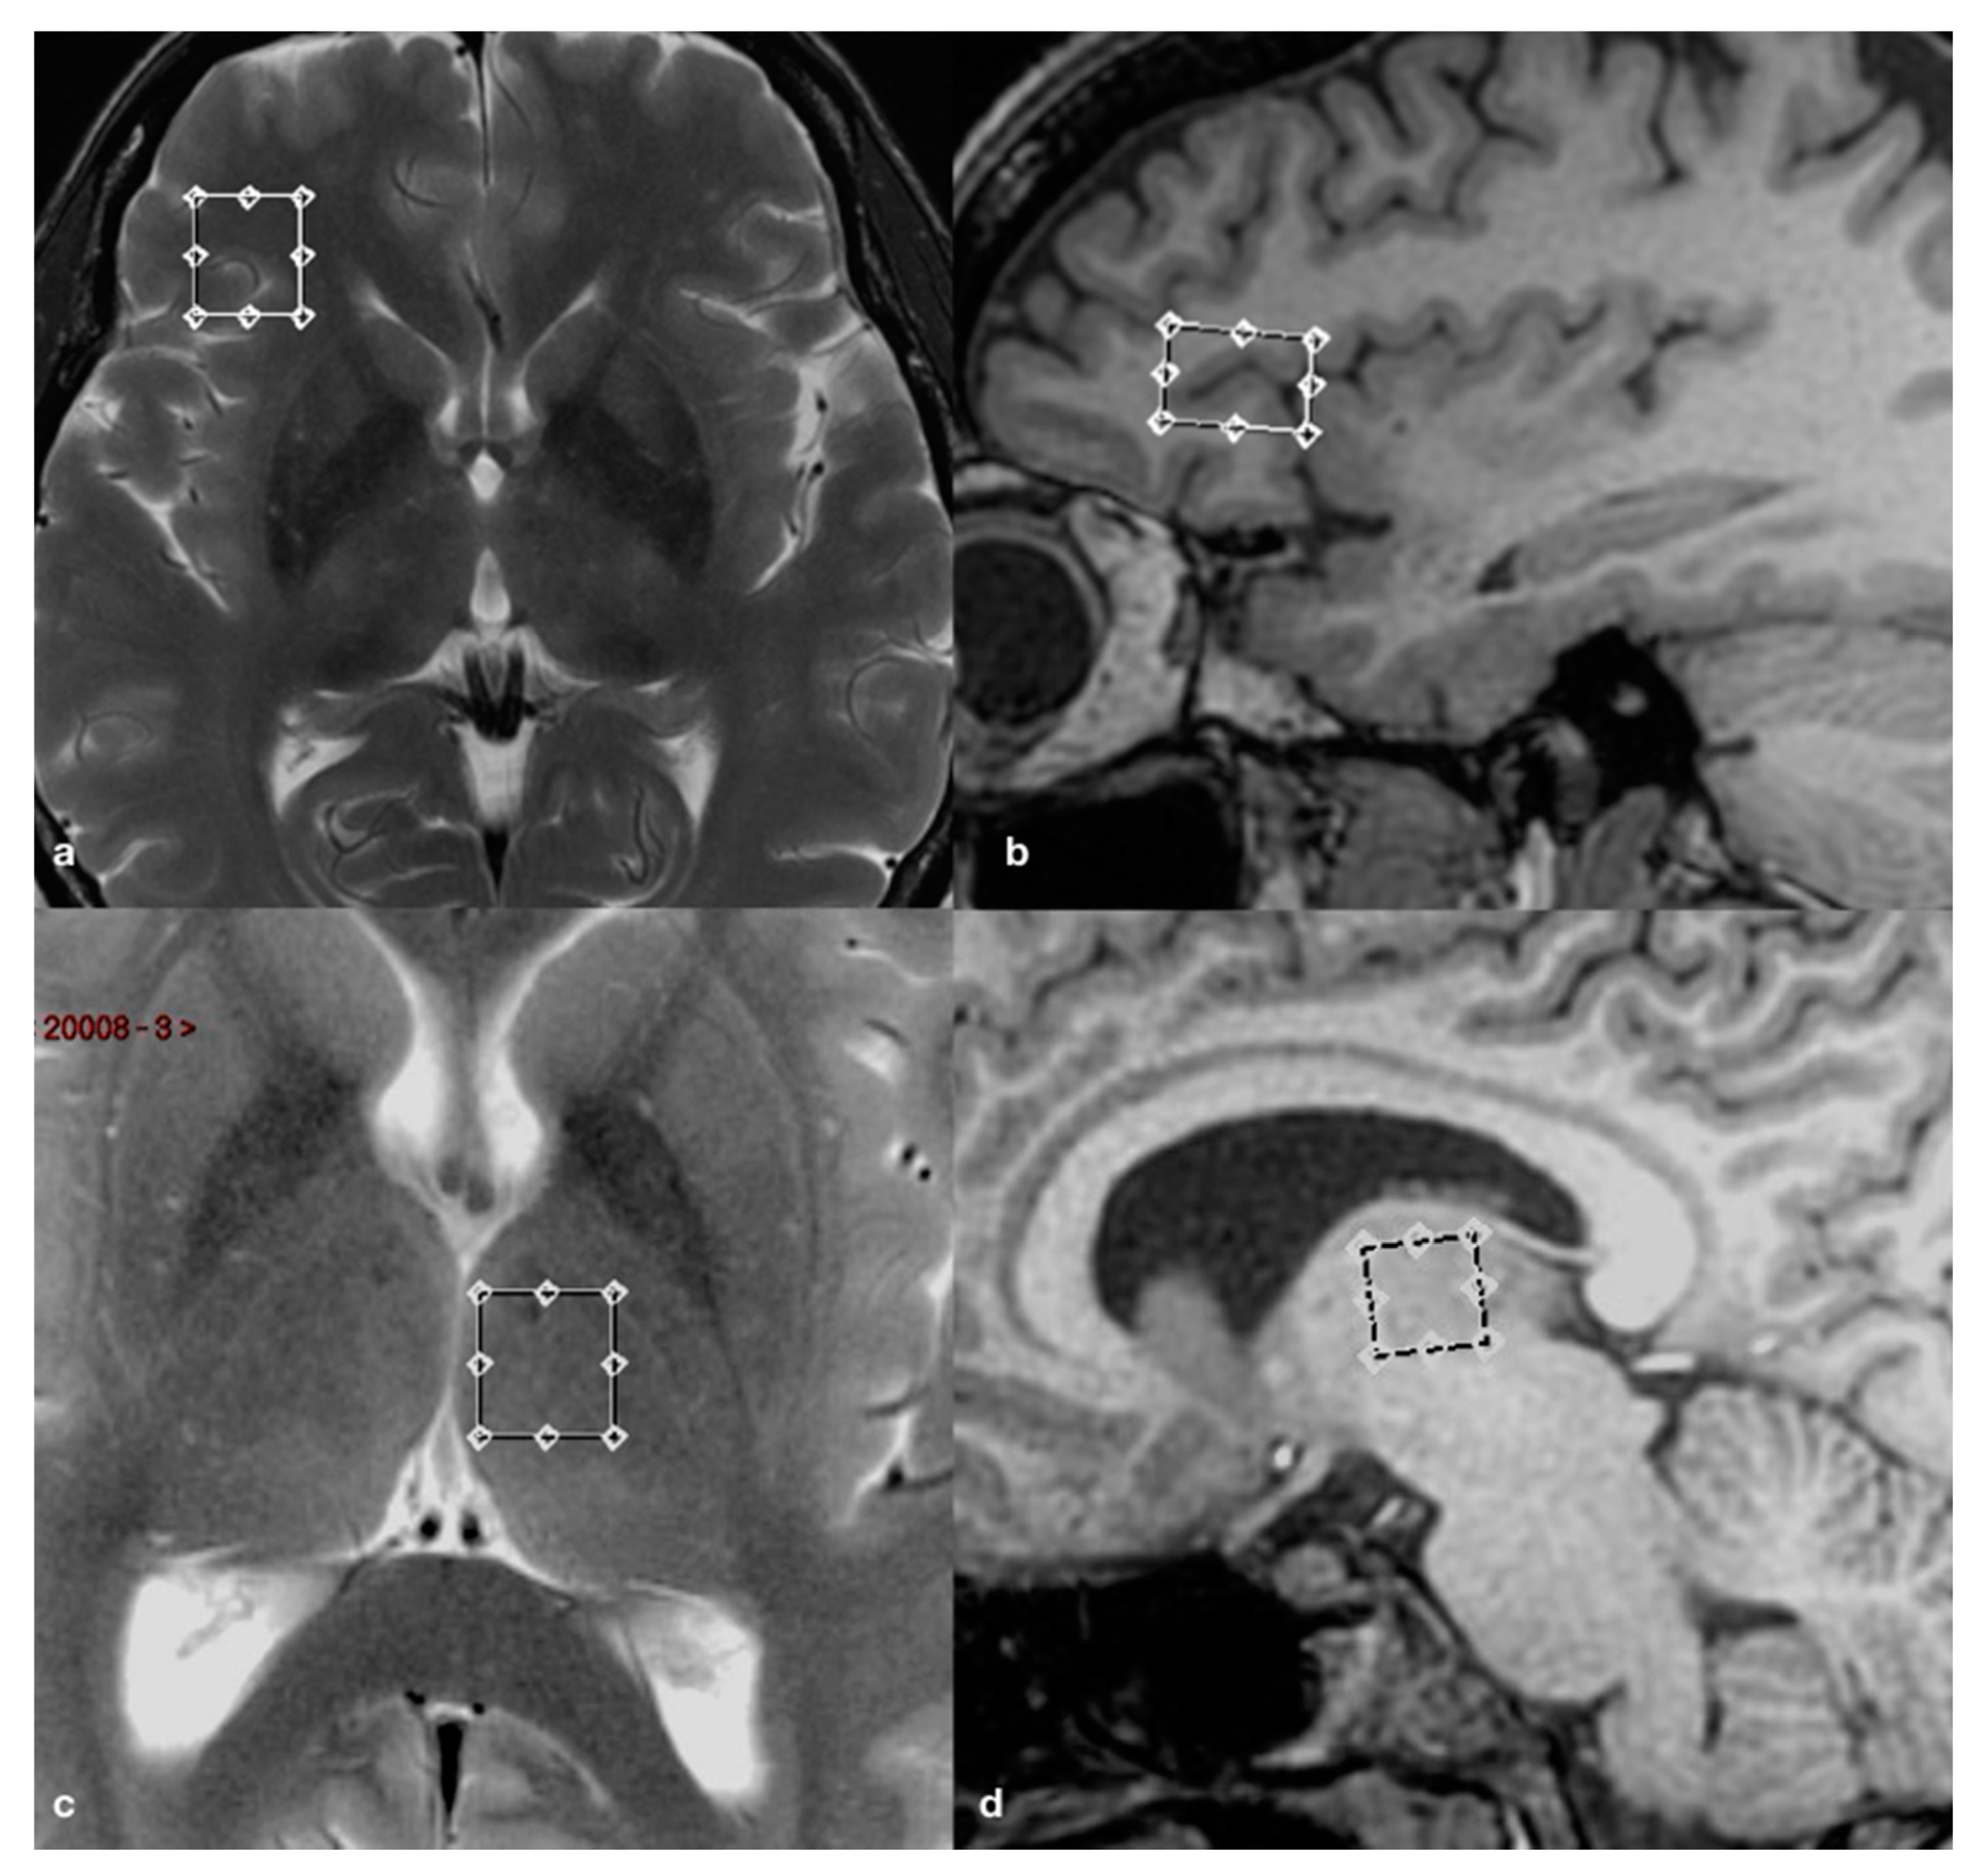

2.2. Brain Imaging and Spectroscopy